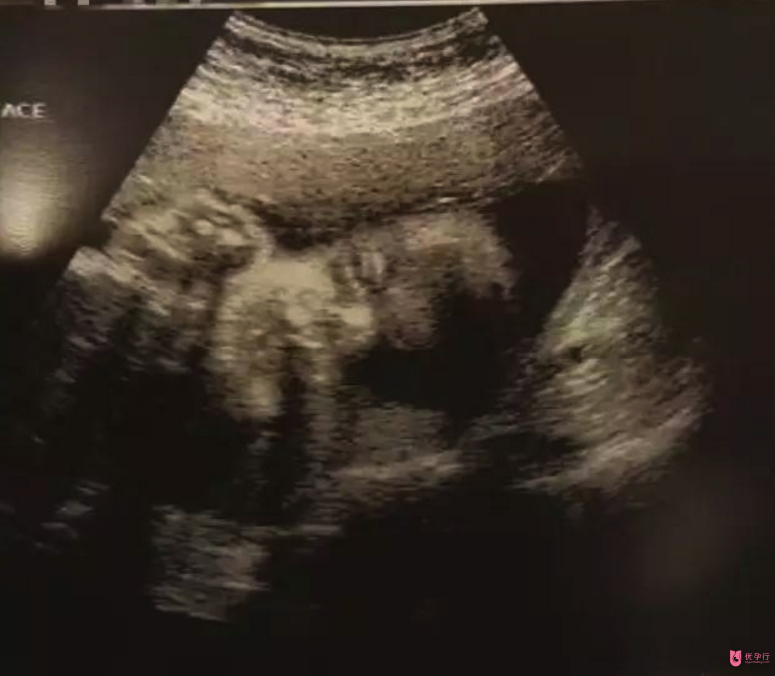

從2004年到2016年,我12年的奮戰(zhàn)史終于成功了,為了呵護(hù)好腹中的,我決定在美好好安胎,等三個(gè)月穩(wěn)定后再回國。8月22日,我去診所做了B超,醫(yī)生微笑著告訴我,已有胎心搏動(dòng),想著腹中還有另外一個(gè)小人兒的心跳,我的內(nèi)心就激動(dòng)。原本以為這一生都不會(huì)懷孕,沒成想,在多年的堅(jiān)守后,我還能懷自己的孩子。并且,我的醫(yī)生告訴我,懷孕和生產(chǎn)對于腺肌癥是有好處的,我還要感謝我的,為我驅(qū)走病痛的折磨。